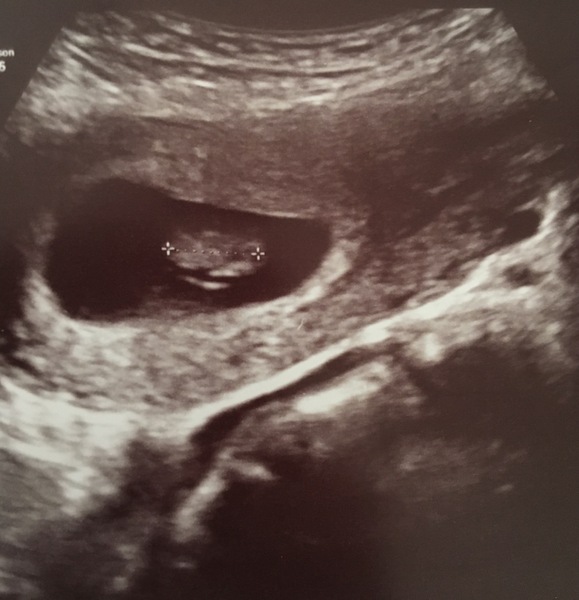

Here is little Beany, who we met today with a lovely heartbeat. I did think I would be more like 8 weeks, but Beany is currently 7w4d and looking good. DH had tears in his eyes. I do worry about being out after seeing a heartbeat last time at 7 weeks but measuring 6, although I’m hoping being a few days out is ok. There was a medical student so the sonographer was really thorough which was helpful- no cysts or fibroids. Also the midwife said that the one off spotting is definitely the progesterone pessary. Next stop is to book the harmony test!